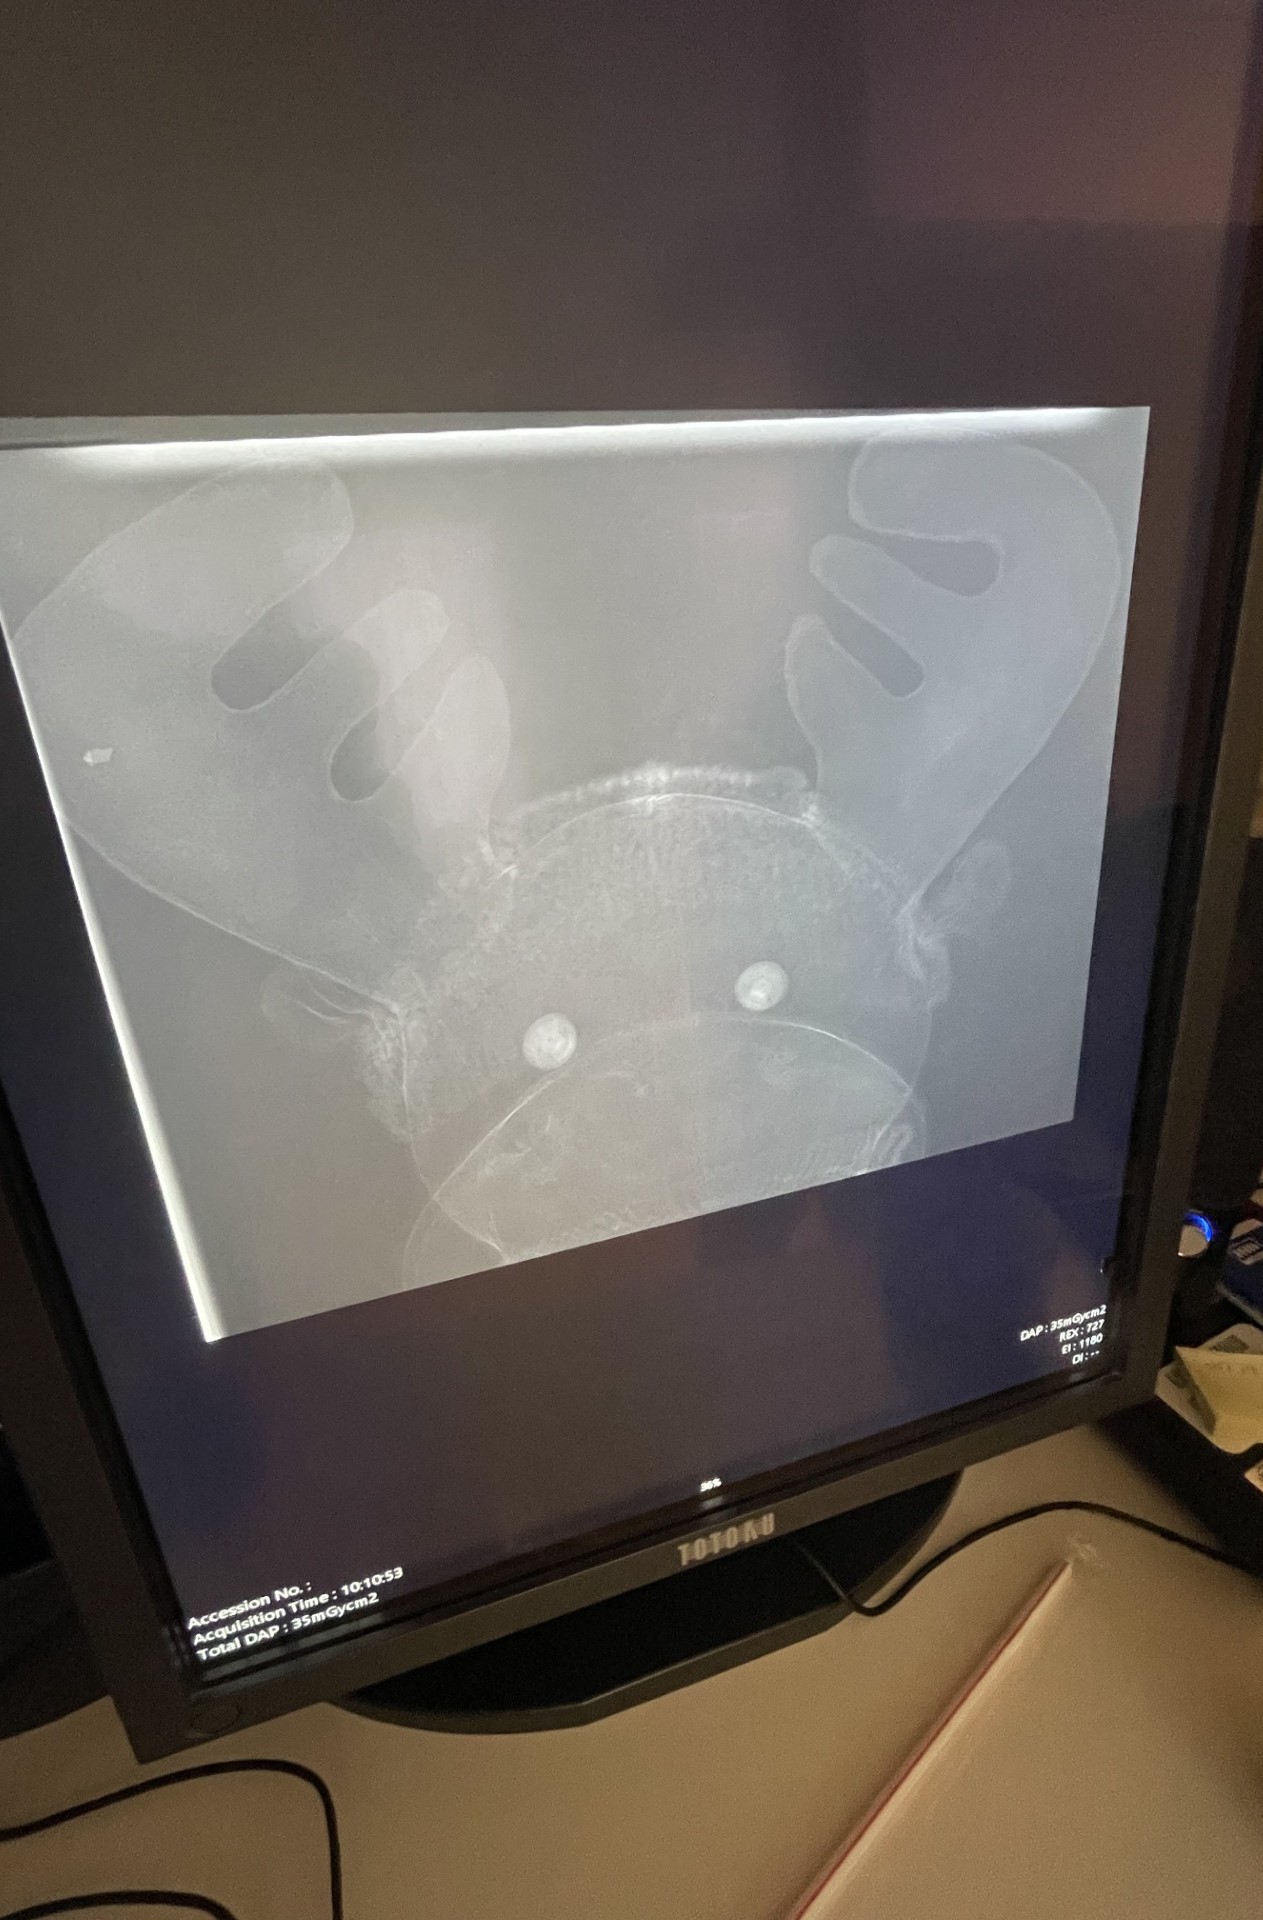

I dag skal vi ta bilde av Eik sin mage. Eik legger seg ned på sengen og later som man er en statue.

Så flyttes det store kameraet over stedet vi skal ta bildet av - kanskje armen, foten eller magen din. Et lys blir skrudd på så vi ser hvor bildet skal tas. Snart tar vi bildet - husk å ligge helt stille... og kanskje gi et lite smil også!

Hvordan ble bildet? Hvis bildet ikke ble helt bra, kanskje vi må ta ett til. Det er viktig at Eik ligger helt stille, om bildet blir litt uskarpt må vi prøve på nytt. Her er et bilde av hodet til Eik. Lurer på om man kan se hva elgen tenker.